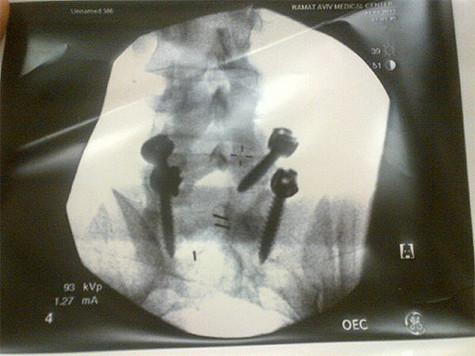

Известный продюсер Яна Рудковская прилетела в Израиль, где в настоящее время находится ее супруг, фигурист Евгений Плющенко. Почти сразу по прибытию на место Рудковскую ждал крайне неприятный сюрприз, о котором она не преминула рассказать в своем «Твиттере». Яну и ее мужа попытались уличить во лжи, ссылаясь на то, что ни в одной из клиник Израиля пациента по фамилии Плющенко нет. Чтобы доказать, что ее муж действительно проходит лечение, и защитить его спортивную репутацию, Яна пошла на беспрецедентный шаг — опубликовала в своем микроблоге не только фото из палаты, в которой лежит Евгений, но и снимок его позвоночника с тремя штифтами.

«Вот с чем теперь придется жить! В правом углу название клиники», — отметила Рудковская.

Напомним, что накануне в одной из израильских клиник Плющенко была сделана операция на позвоночнике, из-за боли в котором фигурист даже был вынужден сняться с Чемпионата Европы в Загребе.